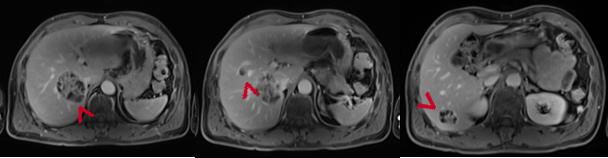

2019年10月复查MRI示:肝多发转移瘤。

MRI示:肝内多发转移灶